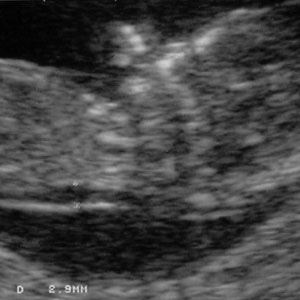

هنگامی که جنین بین 45 تا 84 میلیمتر طول دارد، NT کمتر از 3.5 میلیمتر طبیعی است. NT با رشد جنین افزایش می یابد. تصاویر زیر مقادیر مختلف NT را نشان می دهد.

NT= 2.9 mm:

- جنین با NT=2.9 میلی متر هنوز در محدوده طبیعی است.

- جنین با NT بین 2.9 میلیمتر تا 3.5 میلیمتر، با احتمال بسیار کم در معرض خطر سندرم داون می باشد.